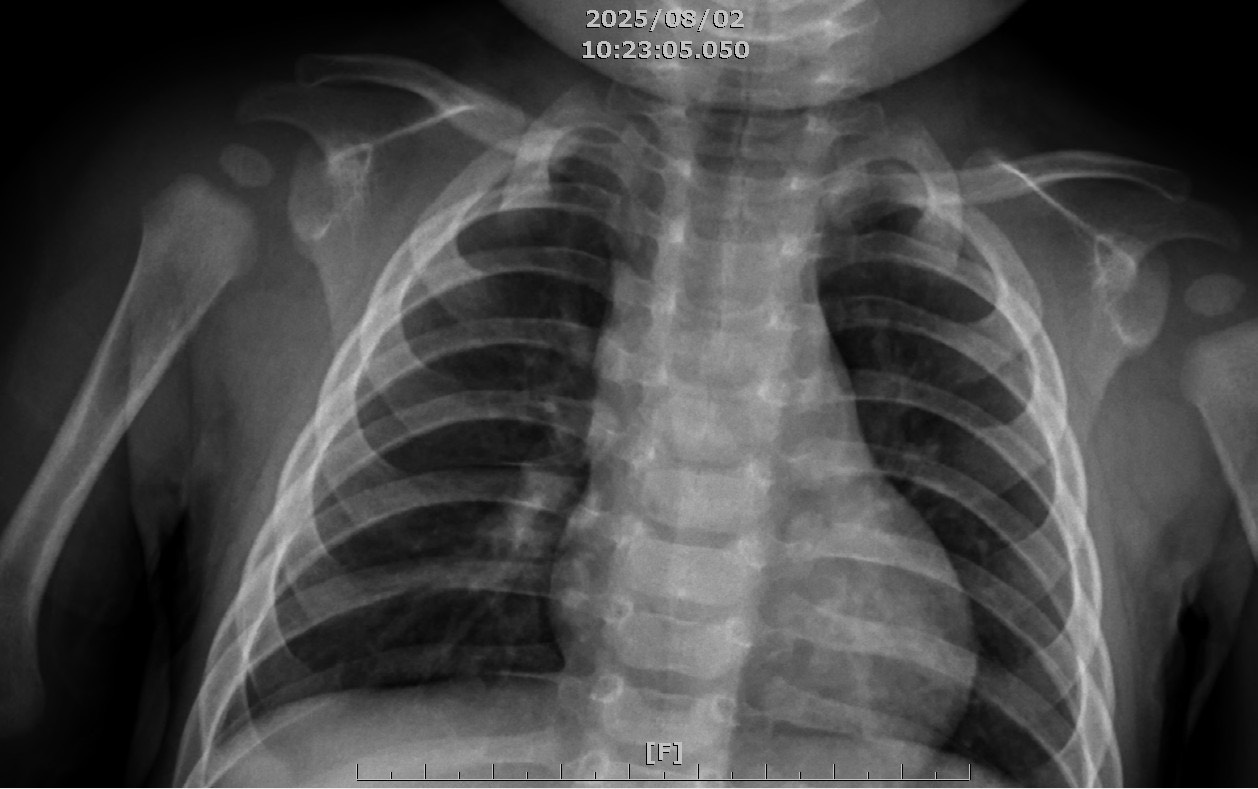

進入秋冬之際,正是各類病毒、細菌蠢蠢欲動的季節。台中醫院上月中就有一名九個月大男童,因為高燒、活動力下降、呼吸喘就醫,結果發現竟是威脅嬰幼兒健康至鉅的「大魔王」肺炎鏈球菌感染;幸運的是,因為男童不但有接種公費肺炎鏈球菌疫苗,連自費的呼吸道融合病毒疫苗、肺炎鏈球菌追加劑、腸病毒七十一型都打了,讓原本嬰幼兒最怕、進展迅速兇猛的肺炎鏈球菌,意外的發病一天後即時被治療且控制,幾乎未威脅到男童的呼吸系統,也未出現腦膜炎、肺炎等嚴重併發症,男童接受2天抗生素治療後退燒且恢復活力,10天抗生素療程結束後順利出院返家。